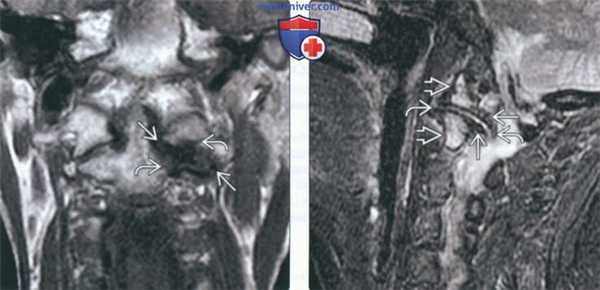

(Слева) На корональной МРТ (Т1 ВИ) определяются признаки ОА бокового атланто-аксиального сустава в виде сужения суставного пространства и наличия остеофитов. Определяется распространенный сигнал низкой интенсив ности в субхондральной кости со стороны обоих компонентов сустава.

(Справа) На сагиттальной MPT (Т2 ВИ) определяются признаки поздней стадии ОА бокового атланто-аксиальною сустава в виде сужения суставного пространства и остеофитов у края сустава. Определяется распространенный сигнал, напоминающий отек, смешанный с очаговым сигналом низкой интенсивности в субхондральной кости.

(Слева) Т1-ВИ, фронтальная проекция: хорошо видны признаки ОА латерального атлантоаксиального сустава. Суставная щель его сужена и выглядит несколько удлиненной на фоне имеющихся остеофитов. Сигнал субхондральной кости обеих суставных поверхностей снижен.

(Справа) Т2-ВИ, сагиттальный срез: картина выраженного дегенеративного поражения латерального атлантоаксиального сустава. Суставная щель его сужена. По краям суставных поверхностей видны остеофиты, костная ткань характеризуется усилением сигнала, напоминающим отек, вперемешку с субхондральными фокусами низкого сигнала.